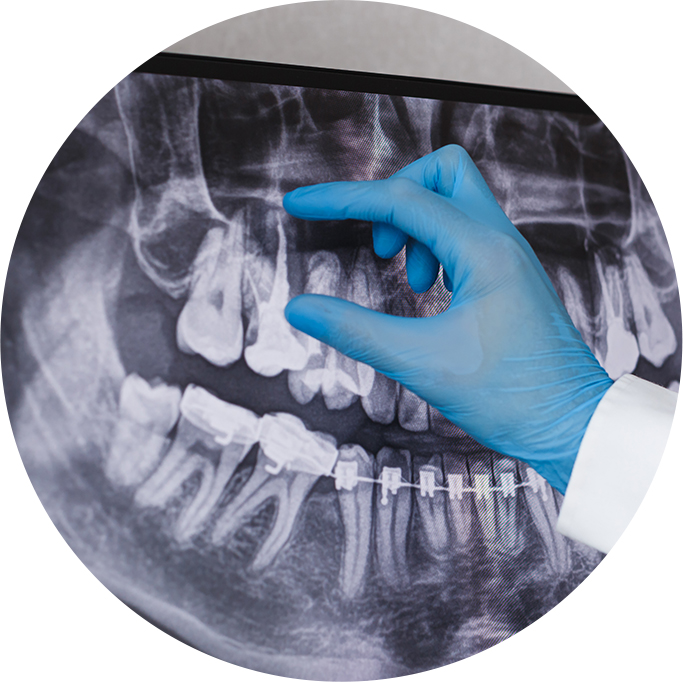

- X-rays are required during treatment.